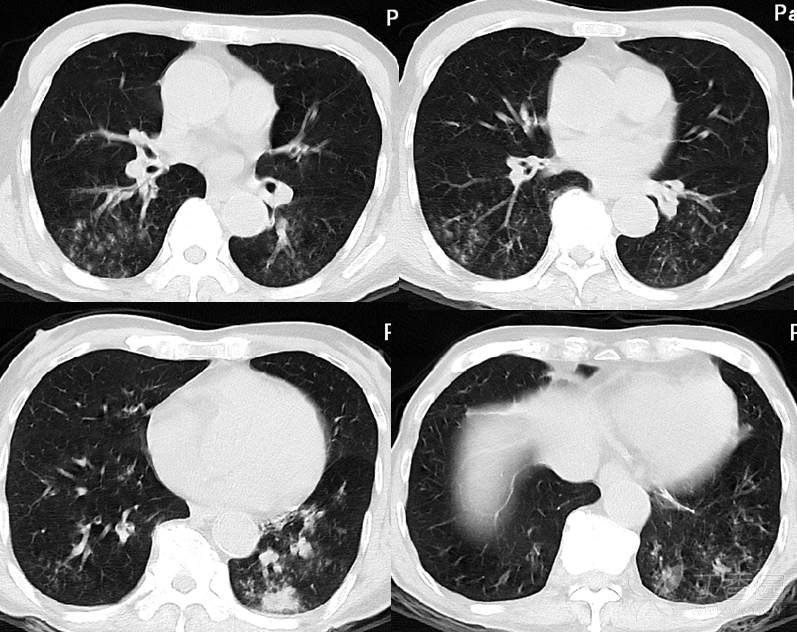

胸部ct扫描时如何识别肺坠积性效应?_患者_体位_影像

图片尺寸1080x444